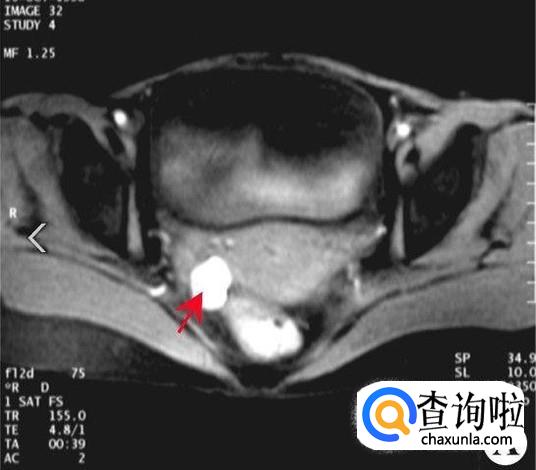

根据专业人士的介绍,巧克力囊肿这种病并不是很严重,巧克力囊肿是在妇科病中比较常见的一种。

女性患上巧克力囊肿可能会出现痛经的情况,而且痛经也是巧克力囊肿患者最容易忽略掉的先找病症。

此外患上巧克力囊肿的女性还可能会出现月经不调的情况,周期可能会缩短,并且经量会增多或者是时间延长。

要想预防巧克力囊肿的话女性应该定期做B超,并且患上巧克力囊肿是可以通过吃中药来进行控制的,但是一定要定期复查直到根治。